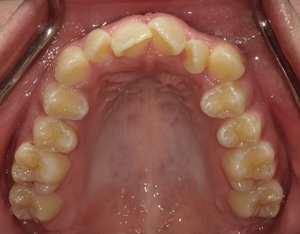

ガタガタとした歯並びや八重歯(叢生)CASE53